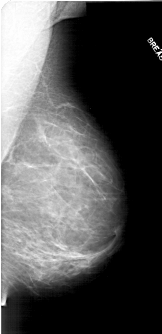

A_1711_1.RIGHT_MLO

RIGHT_CC LINES 6166 PIXELS_PER_LINE 3091 BITS_PER_PIXEL 12 RESOLUTION 43.5 NON_OVERLAY